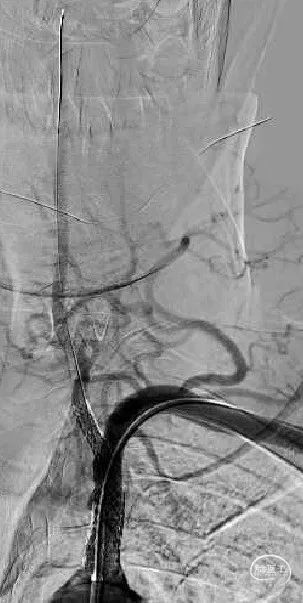

右侧椎动脉造影提示左侧锁骨下动脉盗血,左侧锁骨下动脉闭塞,近端残端较圆钝。

8F Guiding+5F MPA同轴置于左侧锁骨下动脉残端处,反复尝试Command 190cm及Command ES 190cm导丝配合Rebar-18微导管,导丝无法进入真腔,更换Connect 195cm导丝尝试后顺利进入真腔,使用小球囊预扩, Guiding跟到病变远端。

更换Supracore导丝,使用雅培 5*40mm Armada35 球囊扩张后在闭塞起始部植入8*29mm Omnilink支架。

使用雅培 Command导丝顺利超选进入左椎V2段,冠脉3.0*12mm球囊进行扩张,在V18导丝的支撑下,在左侧椎动脉起始部植入一枚雅培4.5*15mm Herculink支架。支架植入后,造影提示椎动脉狭窄得到明显改善。

两侧桡动脉搏动基本对称,两侧肱动脉血压基本对称。